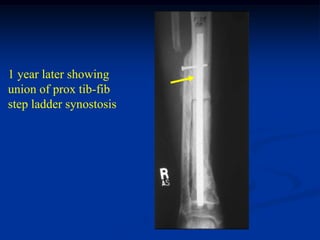

1 year later showing

union of prox tib-fib

step ladder synostosis